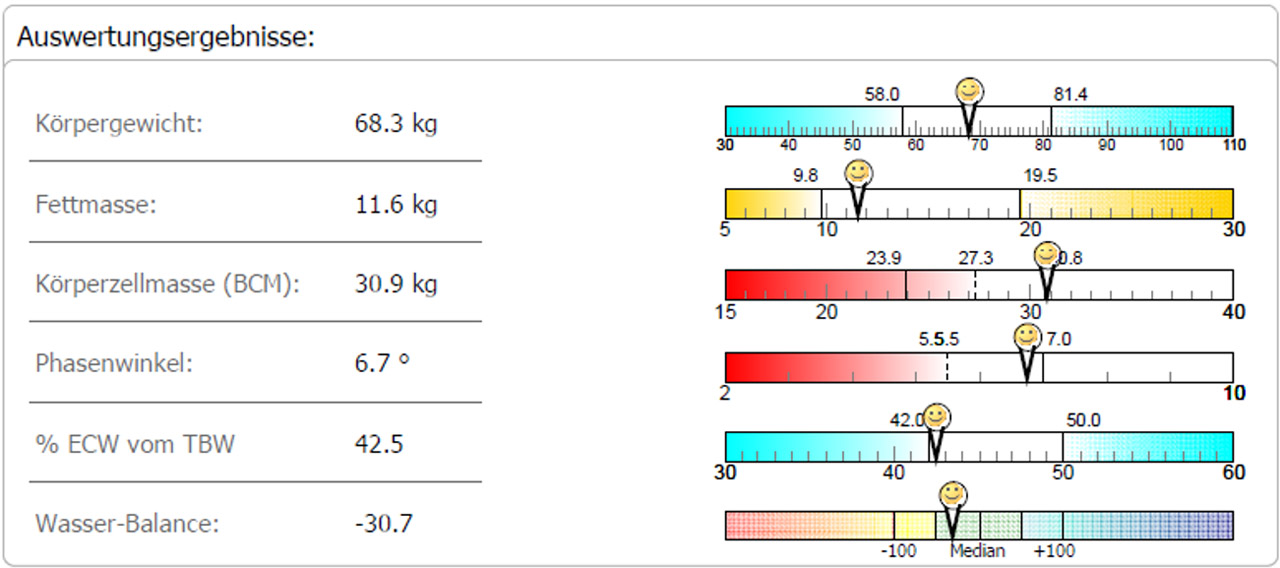

Darstellung der Auswertungs-Ergebnisse

Die Entwicklung und die Wirkungen der Trainingsmassnahmen und begleitender Ernährungsumstellungen können mittels Balkendiagramm dargestellt werden.

Dieser junge Patient macht seit Jahren Krafttraining. Man kann sehen, dass sich der Fettgehalt massiv reduziert hat, die BCM deutlich zugenommen hat und das ECW abgenommen hat.